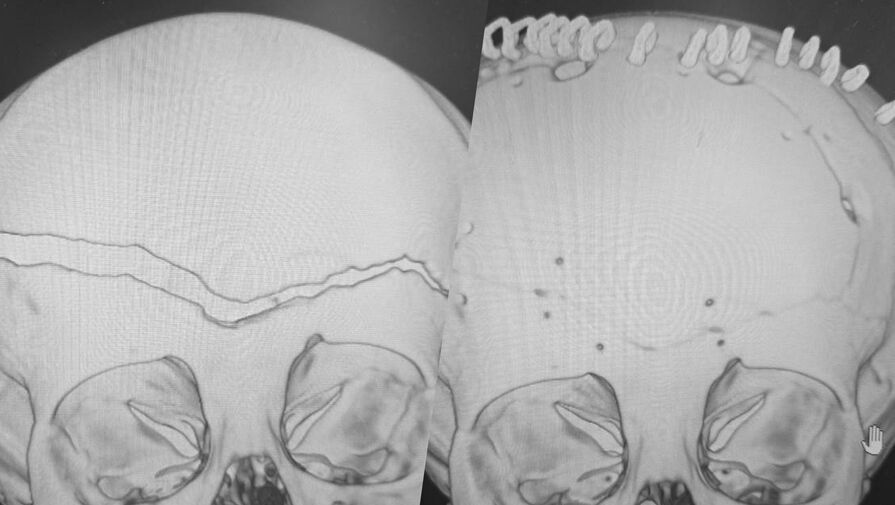

«У ребенка была гигантская эпидуральная гематома и линейный перелом лобной и теменной костей с расхождением линии перелома до 1,5 см», — рассказал заведующий нейрохирургическим отделением ВКБ №2 Сергей Моисеенко, добавив, что у его коллега на счету была каждая минута.